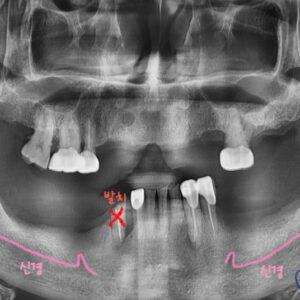

위 앞니(대문니)가 흔들려서 내원하신 환자분입니다.

위 앞니가, 치주염(잇몸병)에 의해

동요도가 심하여 발치가 불가피한 상황입니다.

치아 뿌리를 둘러싸고 있는 치조골 소실이 심한 상태입니다.

발치와 동시에 임플란트 식립 및 골이식을 하기로 합니다.!!!